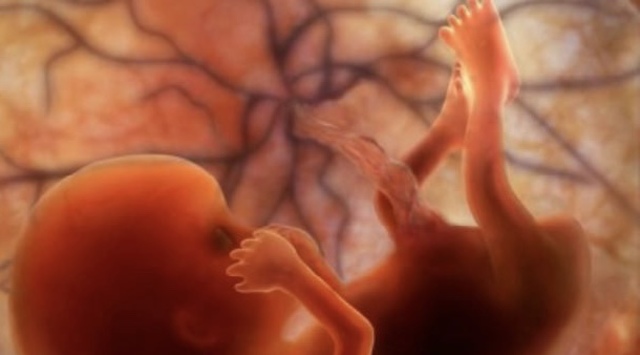

• 8 Semanas (Feto)

8 Semanas (Feto)

*El embrión pasa a llamarse feto

* El saco vitelino se marchita, y la placenta asume la función de alimentar y nutrir al feto.